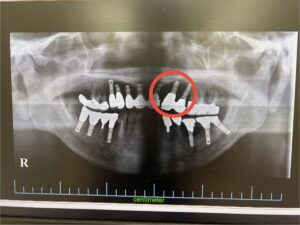

左下のインプラントはしっかりと機能しており、今回は左上の前歯2本に美しいセラミックを装着いたしました。これで、当院で埋入したインプラントは合計13本となります。

術前

術後